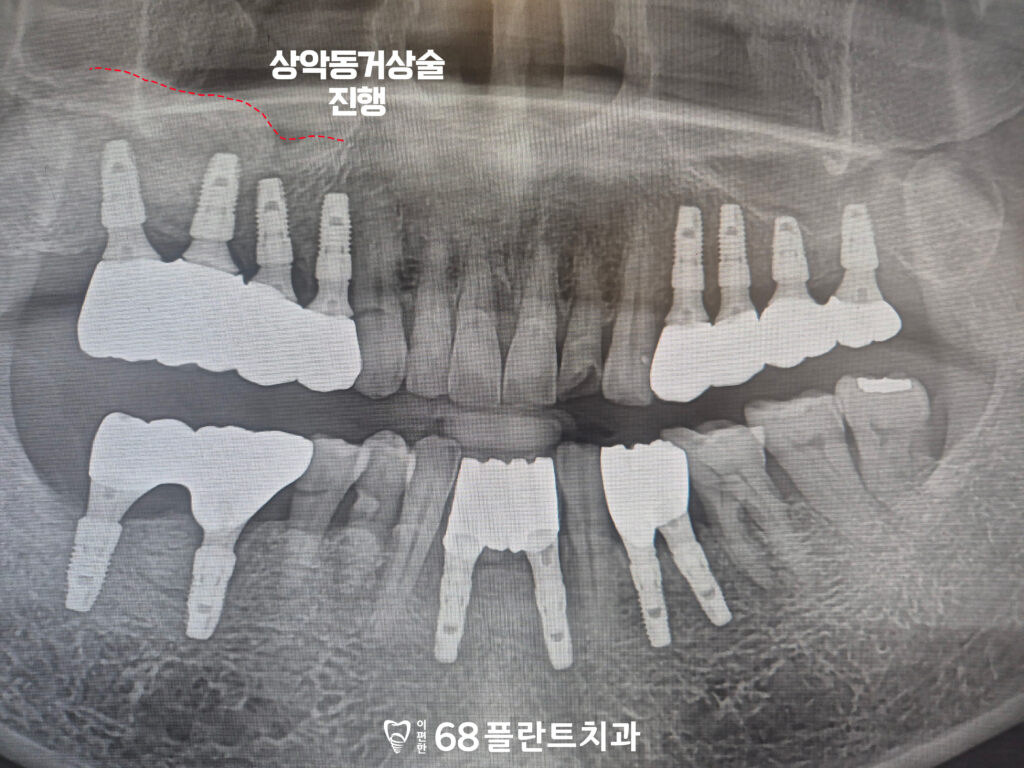

그래서 철산역치과 이편한68플란트에서는

부족한 잇몸뼈를 보완하기 위해

상악동거상술을 먼저 시행한 뒤,

임플란트를 안정적으로 식립하는 방향으로

치료 계획을 수립하였습니다.

먼저 측방으로 접근하여

상악동 막을 조심스럽게 거상한 뒤,

부족한 공간에 골이식재를 채워

임플란트를 식립할 수 있는

기반을 형성하였습니다.

이렇게 상악동거상술을 통해

부족했던 잇몸뼈의 높이를 확보한 뒤,

안정적인 환경을 마련할 수 있었습니다.

이후 임플란트를 정밀한 위치에

식립하였습니다.